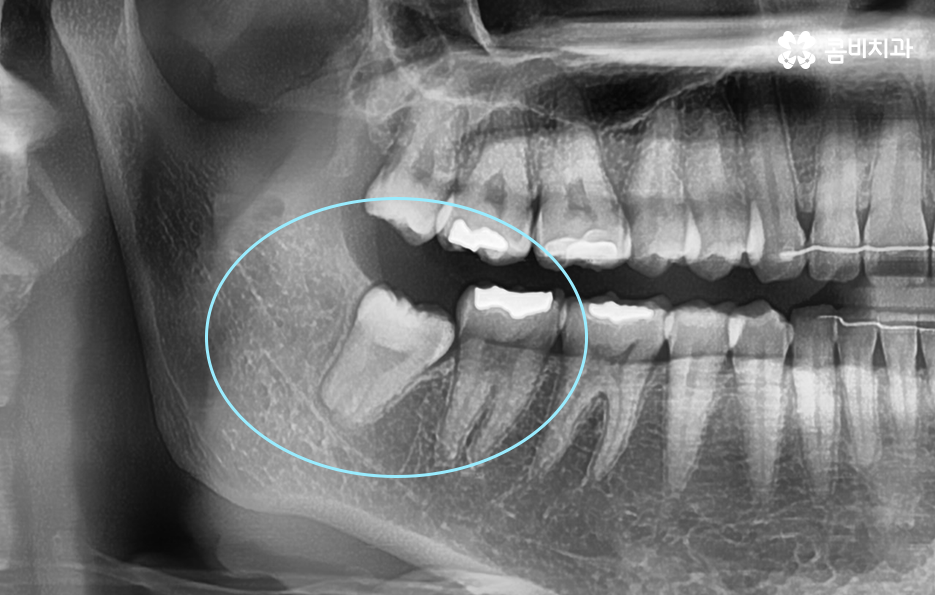

그리고 보편적으로는 윗니의 경우 중력에 의해 사랑니가 똑바로 나오는 경우가 좀더 많다면 아랫니의 경우 누워서 자라는 경우가 좀 더 많이 있는데요. 사랑니는 이처럼 나오는 위치나 방향의 개인차도 크고 정상적으로 똑바로 나온 경우에도 칫솔질이 잘 닿지 않거나 치석이 쌓이기 쉬운 위치이다 보니 결국 발치로 이어지는 경우가 많을 거예요

예를 들어 사랑니의 충치가 어금니의 인접면까지 같이 발생한 경우에는 사랑니 발치 만으로 끝나는 것이 아니라 어금니 치료까지 함께 진행되어야 하는 경우도 있고 사랑니로 인한 염증이 심해진 경우에도 잇몸 치료가 발치와 함께 진행되어야 하는 경우도 있을 거예요

매복사랑니의 경우 당장 발치가 필요하지 않은 경우에도 주기적으로 치과 검진을 통해 사랑니의 상태를 체크할 필요가 있으며 특히 어금니 뿌리 쪽에 안좋은 영향을 주고 있거나 우려가 있다면 발치 계획을 세워야 할 거예요

일반적으로 상악보다는 하악이 하치조 신경과 턱뼈가 근접하기 때문에 좀더 세심한 발치를 해야하며 정상 맹출된 사랑니 보다는 완전 매복되어 있는 사랑니 발치가 고난도의 발치로 분류되고 있어요